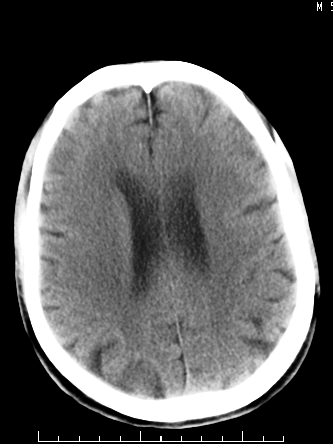

m/50,头昏头痛1月,近3天感觉左半肢体活动不利,自述半年前呈患肺tb,腰穿脑脊液未见特殊改变。现做头颅ct请大家会诊。

考虑颅内感染性病变:结核可能性大。

结核性脑膜炎,结核瘤,梗塞灶三症并存,提示颅内结核感染可能性大。

右侧基底节区缺血性脑梗塞.脑干区考虑结核.

可考虑结核,患者水肿范围大,囊性病灶边缘密度较高,不考虑胶质母细胞瘤